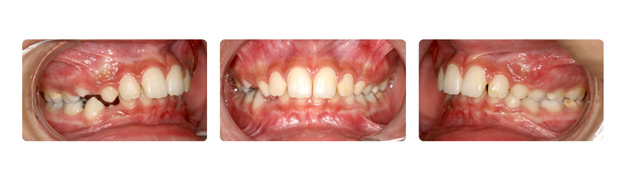

| فک پایین بیمار جلوتر از فک بالا قراردارد وهمچنین دندانهای فک بالا پشت دندانهای پایین قرار گرفته است ودندانهای نیش فک بالا بصورت نهفته می باشد: |

![]() |

| دندان نهفته ی نیش سمت راست در قسمت کام وسمت چپ در زیر لب و بالای دندانها قرار دارد که توسط جراح لثه روی آن برداشته شده وتوسط ارتودنسی و براکتها به جای برده می شود: |